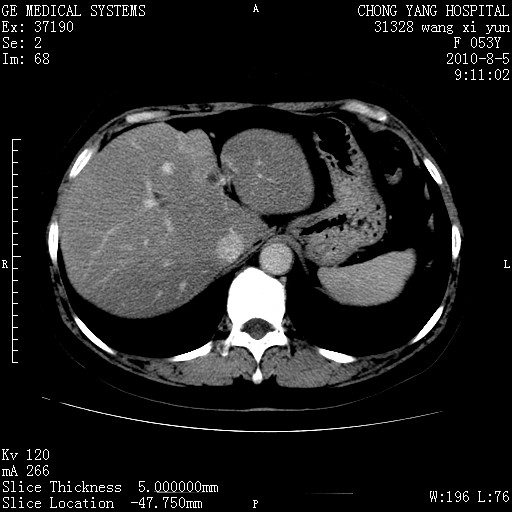

标题: CT28214:F41Y 血尿二十天,建议盆腔平扫加增强。

胆管细胞ca?

1)考虑肝左叶胆管细胞癌。2)脂肪肝。

支持胆管细胞ca。